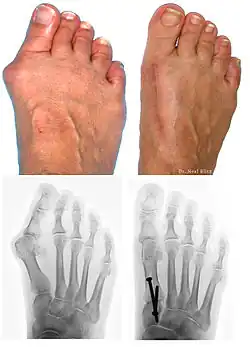

Bunions can be diagnosed and analyzed with a simple x-ray, which should be taken with the weight on the foot.[10] The hallux valgus angle (HVA) is the angle between the long axes of the proximal phalanx and the first metatarsal bone of the big toe. It is considered abnormal if greater than 15–18°.[11] The following HV angles can also be used to grade the severity of hallux valgus:[12]

Surgery

Procedures are designed and chosen to correct a variety of pathologies that may be associated with the bunion. For instance, procedures may address some combination of:

- removing the abnormal bony enlargement of the first metatarsal,

- realigning the first metatarsal bone relative to the adjacent metatarsal bone,

- straightening the great toe relative to the first metatarsal and adjacent toes,

- realigning the cartilaginous surfaces of the great toe joint,

- addressing arthritic changes associated with the great toe joint,

- repositioning the sesamoid bones beneath the first metatarsal bone,

- shortening, lengthening, raising, or lowering the first metatarsal bone,

- correcting any abnormal bowing or misalignment within the great toe,

- connecting two parallel long bones side by side by syndesmosis procedure

At present there are many different bunion surgeries for different effects. The age, health, lifestyle and activity level of the patient may also play a role in the choice of procedure.

Traditional bunion surgery can be performed under local, spinal or general anesthetic. A person who has undergone bunion surgery can expect a 6- to 8-week recovery period during which crutches are usually required to aid mobility. An orthopedic cast is much less common today as newer, more stable procedures and better forms of fixation (stabilizing the bone with screws and other hardware) are used. Hardware may even include absorbable pins that perform their function and are then broken down by the body over the course of months. After recovery long term stiffness or limited range of motion may occur in some patients. Visible or limited scarring may also occur for patients.